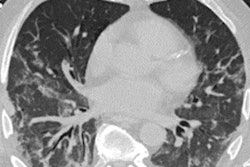

Throughout this year's COVID-19 pandemic, chest CT has proved to be a valuable tool for diagnosing the illness in particular clinical situations -- such as when reverse transcription polymerase chain reaction (RT-PCR) testing isn't readily available or results are delayed.

But the modality has also shown value in assessing the severity of the disease and evaluating ongoing conditions that can plague recovered patients, especially when combined with artificial intelligence (AI), according to several presentations in a scientific session on chest imaging delivered Sunday at the RSNA 2020 meeting.

For the study, Xu and colleagues included 632 chest CT scans from patients with COVID-19 confirmed by RT-PCR testing; of these, 69 patients were admitted to the ICU and 563 were not. The team developed a whole-lung segmentation algorithm and assessed its effectiveness when used with CT by overall accuracy, sensitivity, and specificity.

"Based upon chest CT alone, AI-based deep-learning algorithms can reasonably predict clinical outcomes such as ICU admission in patients with COVID-19 who underwent CT and PCR on the day of admission," Xu concluded. "The model is feasible with reasonable accuracy and specificity of prediction."

Barbosa and colleagues developed a way to quantify the percentage of lung volume involved in airspace disease on chest x-rays using a convolutional neural network (CNN) algorithm based on 1,000 chest CT scans of COVID-19 patients. The researchers used a test set of 86 patients with positive RT-PCR results who had chest CT and chest x-ray less than 48 hours apart.

The algorithm projected the CT exams' 3D lung and airspace disease segmentation on reconstructed x-rays using quantitative maps of lung tissue thickness and manifestations of airspace disease.

The group found that the CNN-reconstructed x-rays quantified airspace disease at least as well as the human CT exam readers: CT had a rate of 24.3%, while the CNN's digitally reconstructed x-rays had a rate of 24.4%.